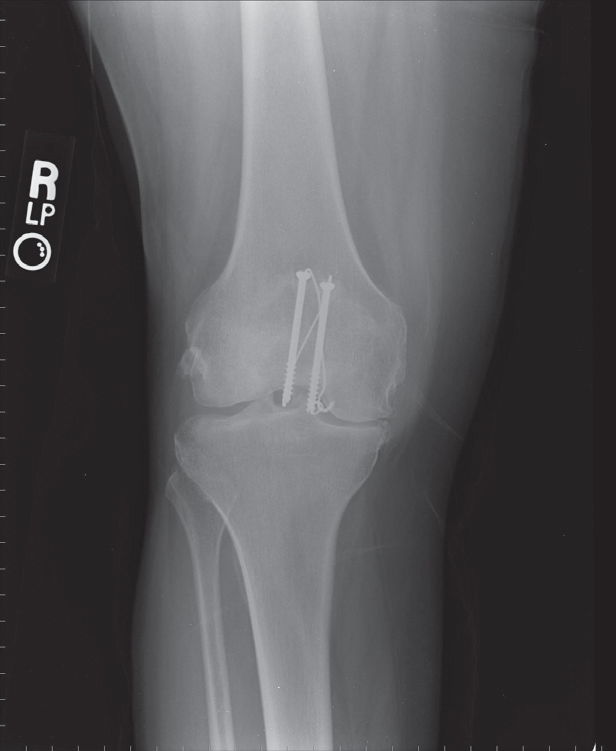

Røntgen

i 2 planer.

Dislocerede

frakturer

Indlægges til åben osteosyntese.

Postoperativ rtg kontrol.